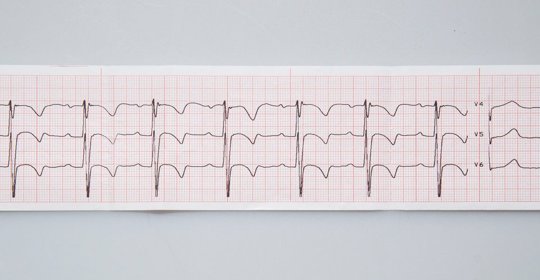

產後心電圖複查

女性在生產後進行心電圖複查的目的主要是明確是否有心臟方面的疾病。如果之前存在心臟方面的疾病,在懷孕期間病情有可能會出現變化,因此需要在分娩之後及時的做心電圖檢查,並且根據結果採取相應的處理措施。

兒童心電圖要做多久

正常情況下,兒童的心電圖檢查時間在10-30分鐘。如果需要進行24小時動態心電圖、心臟事件監測等,則可能需要連續觀察24-72個小時。

兒童心電圖的形成

在進行心電圖檢查時,需要將兩個導聯連線到胸前和手腕上。第一個導聯連線到右胸鎖骨中線第2肋間的位置,第二個導聯連線到左胸部鎖骨中線第5肋間的位置,然後透過肢體導聯轉換為V1-V6導聯。